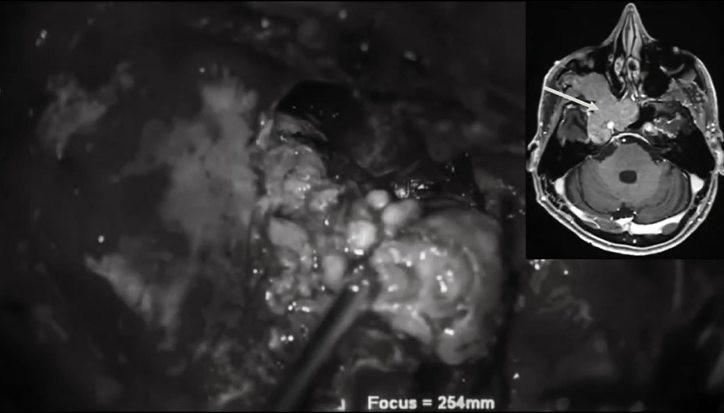

福教授在了解了Leo的具體病史情況及目前腫瘤情況后,制定了詳細(xì)的手術(shù)計劃。手術(shù)中福教授通過手術(shù)顯微鏡、神經(jīng)內(nèi)鏡的實時恰當(dāng)互補(bǔ),能使得術(shù)區(qū)得到更好地暴露,減少患者神經(jīng)損傷、增加腫瘤切除率。

顯微鏡外科手術(shù)分步取出腫瘤圖解

后顱窩部位腫瘤順利切除